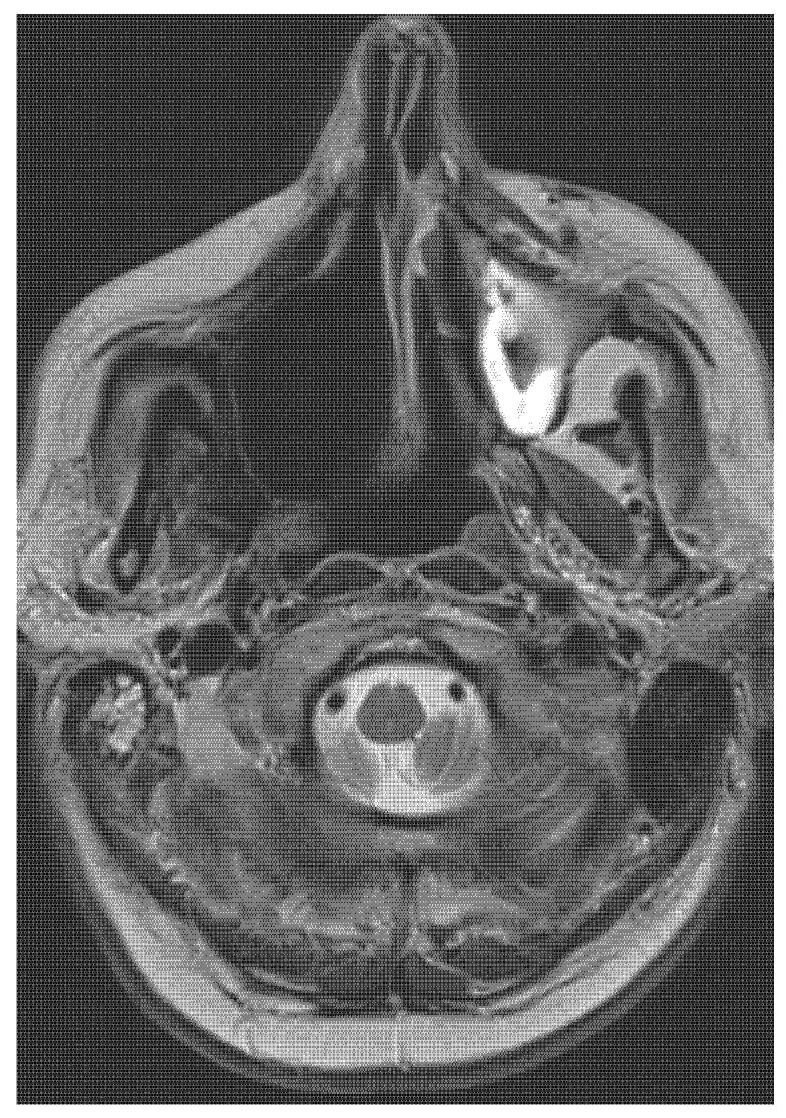

Sarcomas in the head and neck area are rare diseases with an incidence of under 1% of all head and neck malignant tumours. Osteosarcomas or osteogenic sarcomas consist of neoplastic cells that produce osteoid bone or immature bone. Sarcomas develop more in the mandible than the maxilla. The exact diagnosis of different types of sarcomas is based on the immunohistochemical investigation. These rare tumours are of mesenchymal origin; osteosarcomas and chondrosarcomas are the most common types-Ewing's sarcomas. The use of proton beam radiotherapy in the treatment of osteosarcoma of the maxilla is rarely reported in the literature. We present a case of successfully treated (surgery and proton beam radiotherapy) poorly differentiated highly aggressive osteosarcoma in the ethmoids and maxillary sinus and morbidity after the treatment. We were presented with a case of a 65-year-old man with anaesthesia and palsy of the right face. The stomatology department performed the extraction of a tooth. One month later, the wound was still open. The histology showed an osteogenic sarcoma in the area of the wound. The oncologist and maxillofacial surgeons in a catchment hospital recommended a nonsurgical approach. Hence, we performed a radical maxillectomy and ethmoidectomy, after which we continued with proton bean radiotherapy. The patient is now five years after therapy without signs of sarcoma; however, he has blindness in the right eye and reduced vision in the left eye, as well as gliosis of the brain, vertigo, tinnitus, trismus, and ancylostomiases. Head and neck osteosarcomas treatment is considered a complex multidisciplinary task. It is currently argued that there is no clear therapeutic protocol for successful treatment. Innovations in treatment modalities such as proton beam radiotherapy appear to have potential, although their effects on long-term morbidity and survival outcomes are still undetermined. We present a rare case report of an osteosarcoma of the maxilla involving an innovative, successful treatment procedure combining surgical excision followed by proton beam radiotherapy. This treatment approach may enable maximum tumour control. This protocol has not been adequately described in the world literature for this diagnosis.

头颈部肉瘤是一种罕见疾病,发病率低于所有头颈部恶性肿瘤的 1%。骨肉瘤或成骨肉瘤由产生骨样骨或未成熟骨的肿瘤细胞组成。肉瘤在下颌骨比上颌骨更常见。不同类型肉瘤的准确诊断基于免疫组织化学研究。这些罕见的肿瘤来源于间充质;骨肉瘤和软骨肉瘤是最常见的类型——尤因肉瘤。质子束放疗在治疗上颌骨骨肉瘤中的应用在文献中很少报道。我们报告了一例成功治疗(手术和质子束放疗)的筛窦和上颌窦未分化高度侵袭性骨肉瘤病例,以及治疗后的发病率。我们报告了一例 65 岁男性,出现右侧面部麻醉和瘫痪。口腔科进行了拔牙。一个月后,伤口仍未愈合。组织学显示伤口处有骨肉瘤。收治医院的肿瘤学家和颌面外科医生建议采用非手术方法。因此,我们进行了根治性上颌骨切除术和筛窦切除术,之后继续进行质子束放疗。患者在治疗后五年无肉瘤迹象,但右眼失明,左眼视力下降,同时伴有脑胶质增生、眩晕、耳鸣、牙关紧闭和Ancylostomiases。头颈部骨肉瘤的治疗被认为是一项复杂的多学科任务。目前认为,对于成功治疗,尚无明确的治疗方案。治疗方式的创新,如质子束放疗,似乎具有潜力,尽管其对长期发病率和生存结果的影响仍不确定。我们报告了一例罕见的上颌骨肉瘤病例,采用了一种创新的、成功的治疗方法,结合了手术切除和质子束放疗。这种治疗方法可能能够最大限度地控制肿瘤。这种方案在世界范围内针对这一诊断的文献中尚未得到充分描述。